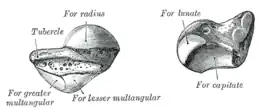

Le scaphoïde est l'os le plus latéral (ou externe) et le plus volumineux de la rangée proximale (ou supérieure) du carpe. Il a une forme un peu allongée, dirigée vers le bas, le côté latéral et un peu en avant.

Pôle proximal

Le pôle proximal est le plus volumineux.

Sa face supérieure est une surface articulaire convexe et regarde en haut et latéralement. Elle s'articule avec le radius au sein de l'articulation radio-carpienne.

Sa face latérale présente un sillon pour le passage de l'artère radiale.

Sa face médiale est articulaire avec l'os lunatum.

Pôle distal

Le pôle distal présente une saillie au niveau de sa partie antéro-latérale, le tubercule du scaphoïde, sur lequel s'insère le ligament collatéral latéral du carpe, le rétinaculum des fléchisseurs et le muscle court abducteur du pouce.

Son bord médial présente une surface articulaire concave orientée médialement et en bas avec la tête de l'os capitatum.

Sa face inférieure est convexe. Elle présente deux facettes articulaires quadrilatères séparées par une crête arrondie.La facette latérale s'articule avec l'os trapèze et la facette médiale avec l'os trapézoïde.